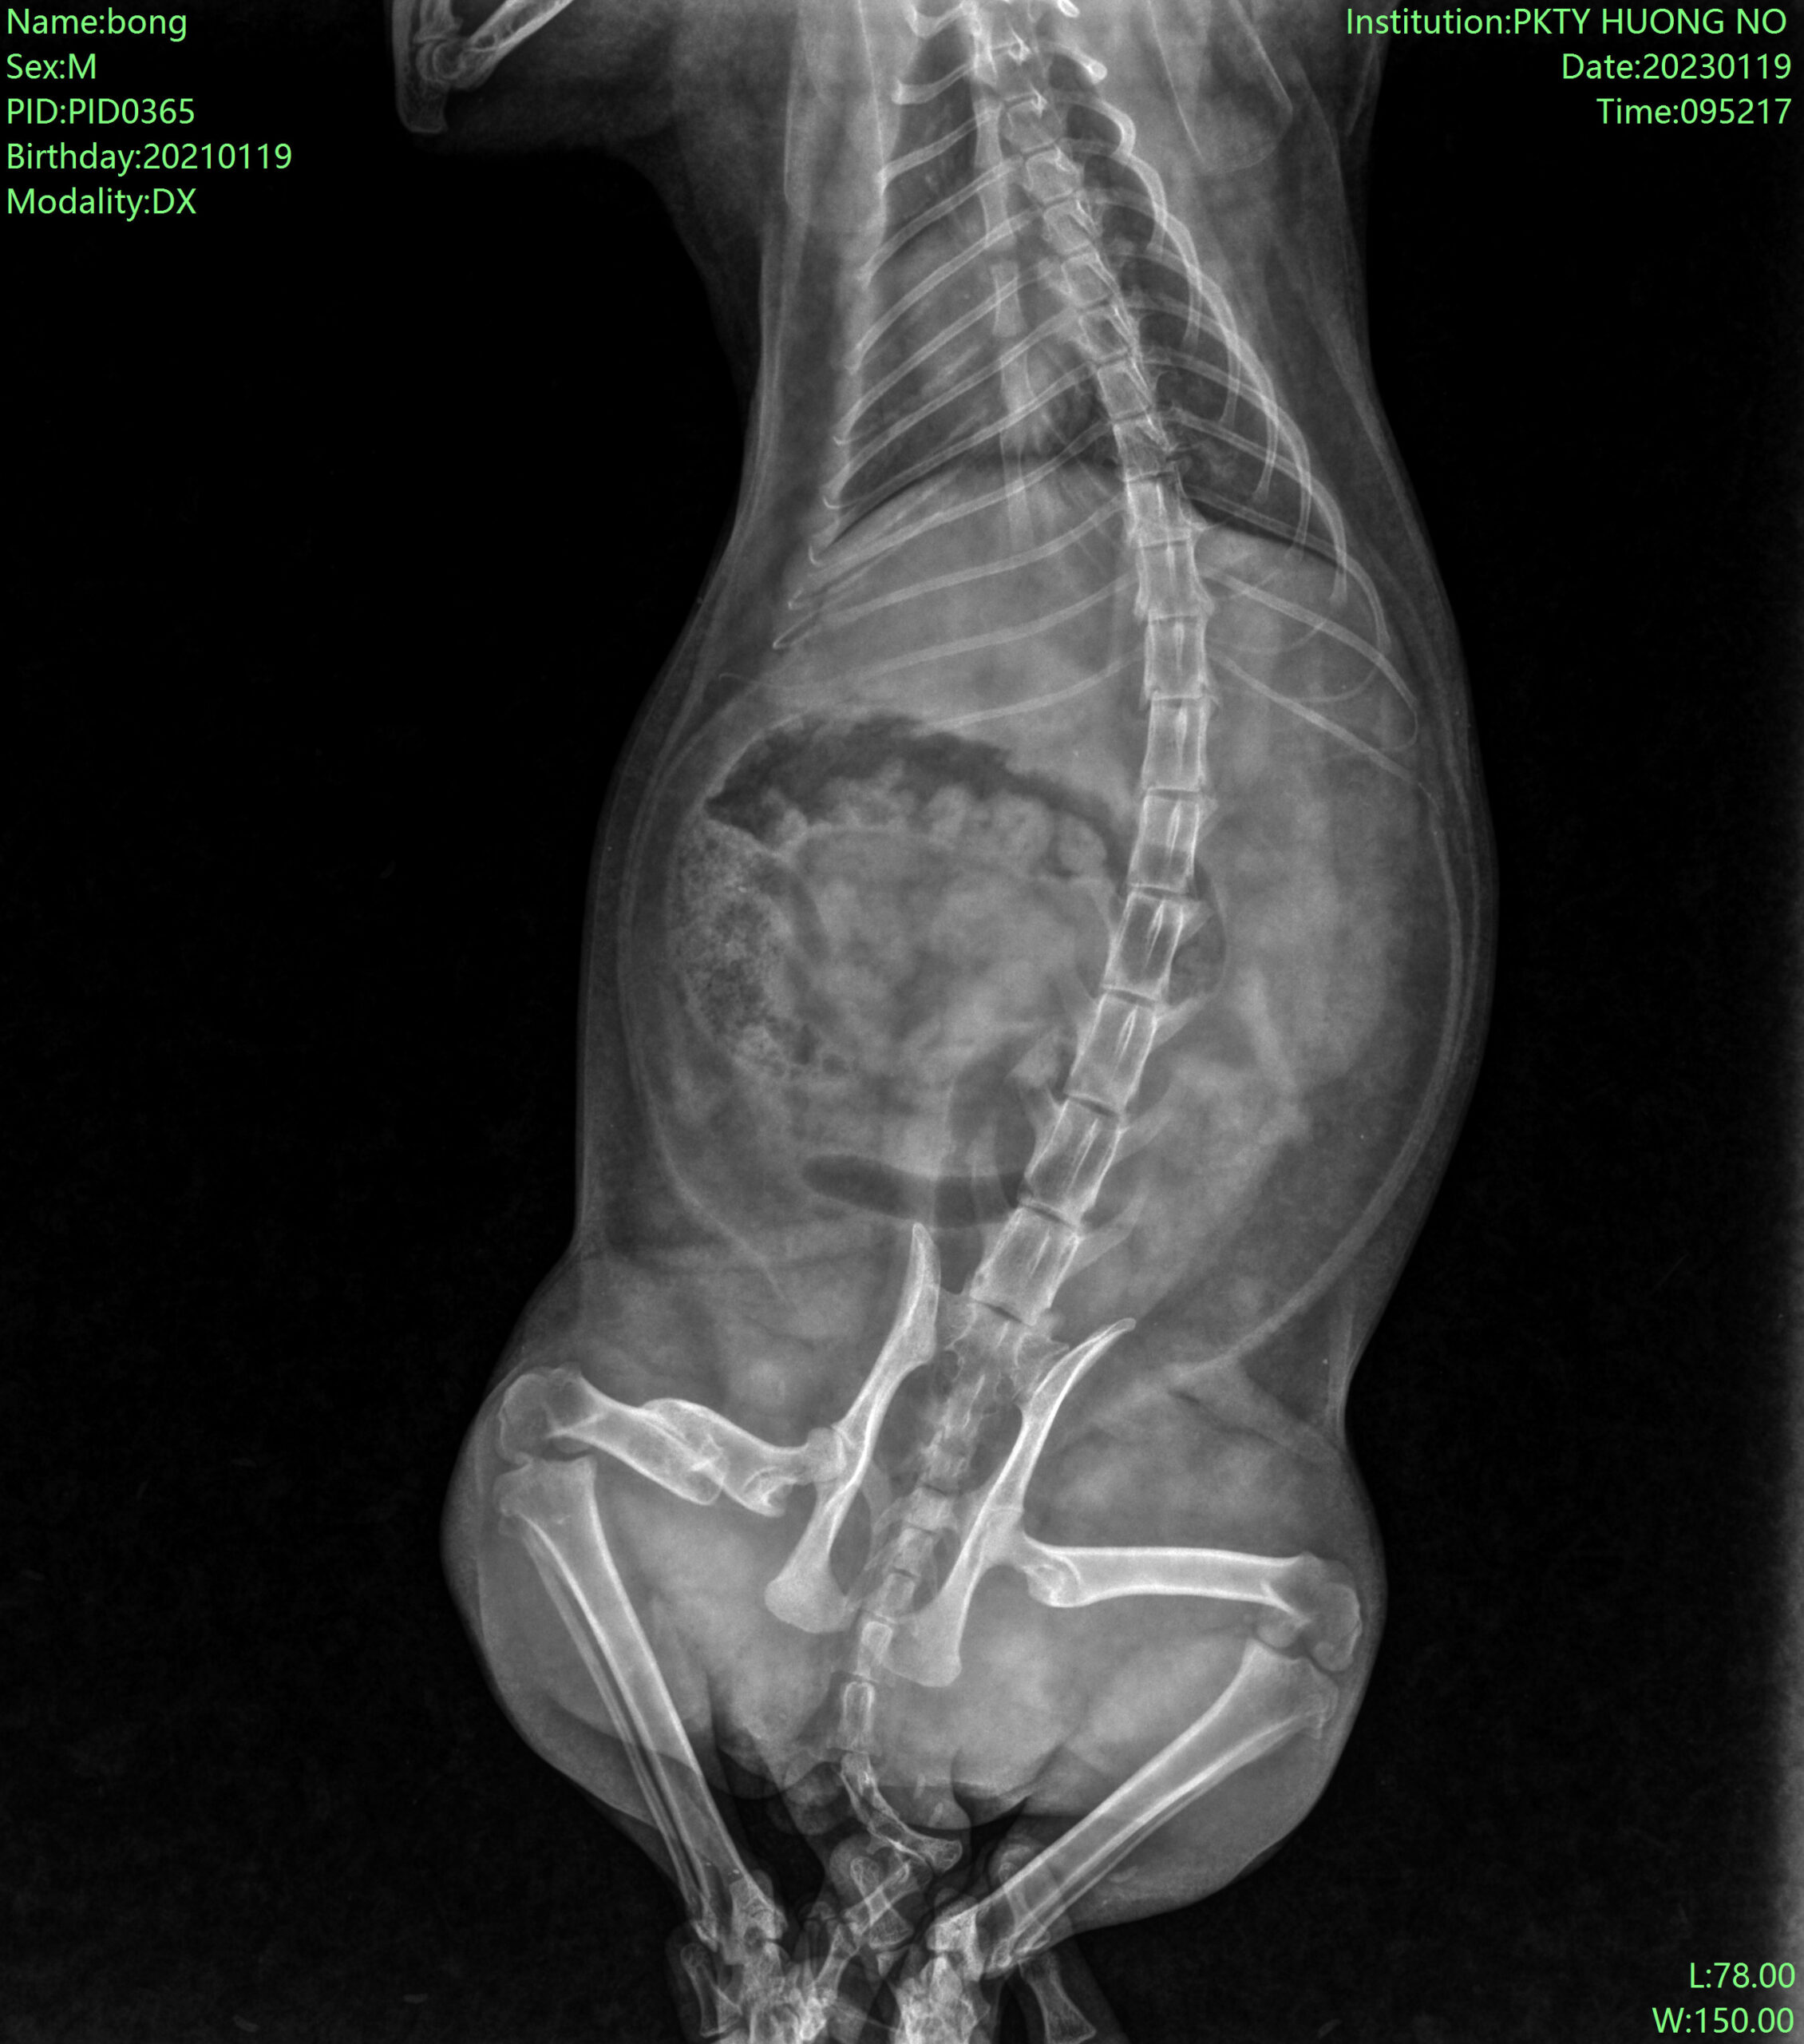

Một ca mổ xương thành công tốt đẹp được thực hiện tại Thú Cưng Hương Nở Phú Lợi vào những ngày giáp Tết AL (28 Tết Quý Mão 2023):

Trước phẫu thuật: